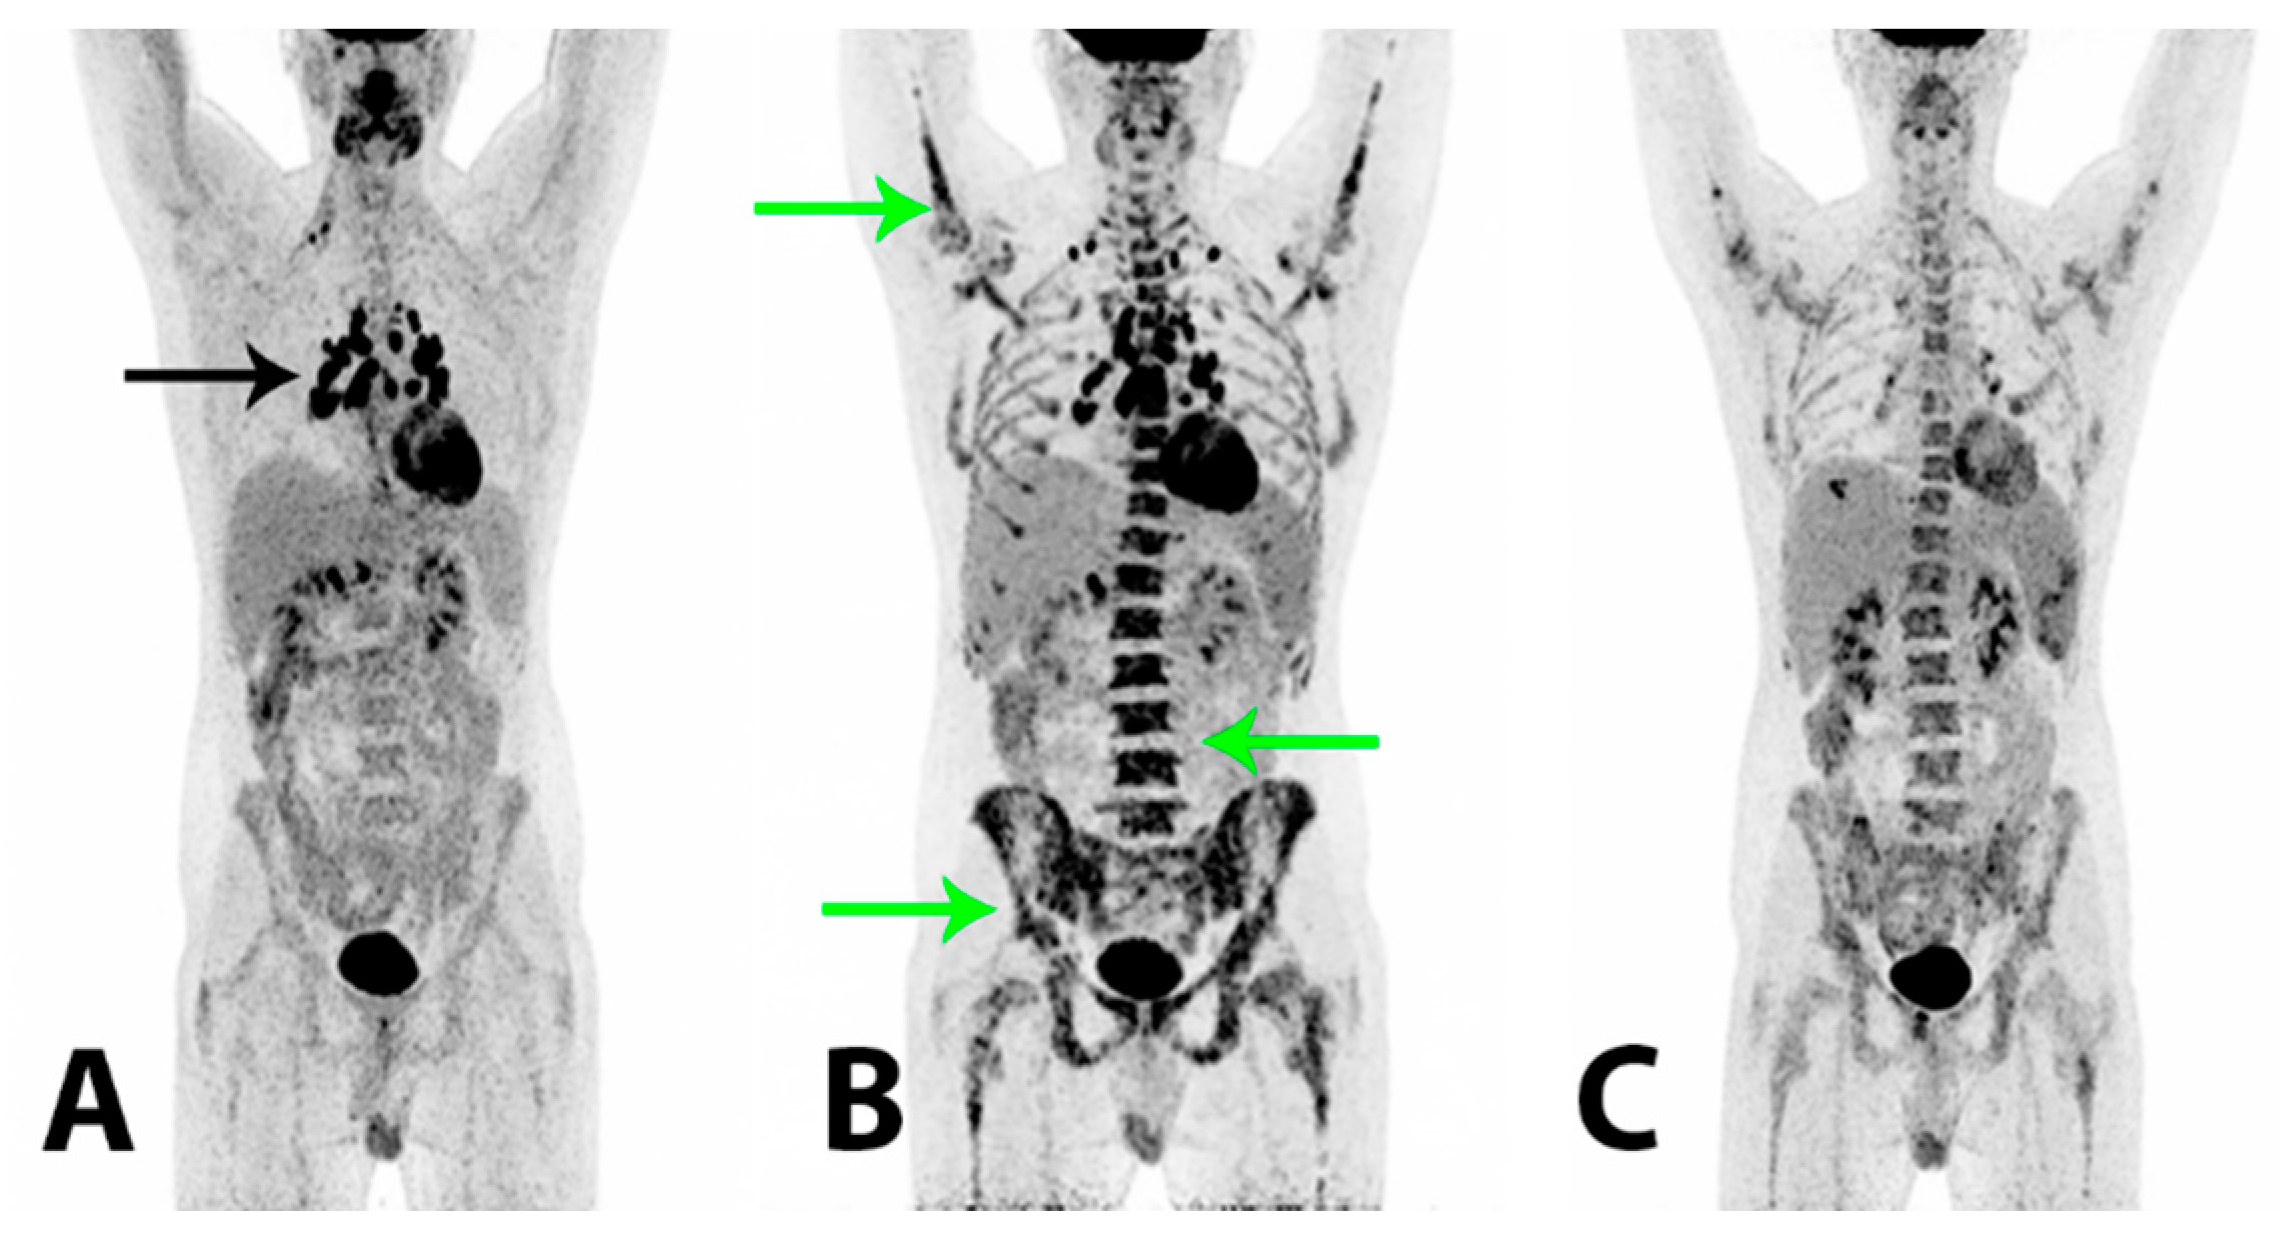

Figure 4. To reduce the risk of HS relapse, an experimental therapeutic approach with high-dose chemotherapy administering a BEAM (carmustine + etoposide + cytarabine + melphalan) regimen and a subsequent autologous stem cell transplant (SCT) was initiated. The patient tolerated the treatment well and at follow-up +60 days after BEAM/SCT the regeneration of bone marrow was considered complete and the tumor marker plasma LDH was still within the reference range (157 U/L). 2-[18F]FDG PET/CT (A) demonstrated a metabolic CR and a further morphological PR. There were now relatively symmetrically localized, metabolically active lymph nodes at the right root of the neck, in both sides of the mediastinum and the lung hilum (black arrow), compatible with possible granulomatous inflammation. Two months later the patient reported a gradual worsening of bone pain in the lumbar and pelvic region. The plasma LDH was now elevated (450 U/L) and thrombocyte and hemoglobin levels were low. A relapse of HS was suspected, which was confirmed by a bone marrow biopsy that showed a massive infiltration of almost 100% of malignant histiocytic cells with blastoid morphology and an immunohistochemical profile similar to previous specimens. Findings on 2-[18F]FDG PET/CT (B) were compatible with a relapse, demonstrating a heterogeneous, pathologically increased FDG-uptake in the bone marrow in the axial and peripheral skeleton (green arrows). There were metabolically active lymph nodes above and now also below the diaphragm. A malignant bone marrow infiltration with a myeloid expansion was considered the cause of the patient’s bone pain. The plasma LDH rose rapidly to 5100 U/L and salvage therapy with an acute myelogenous leukemia regime (CLAG-M; cladribine + cytarabine + mitoxantrone) was initiated. The treatment had a good effect on the patient’s bone pain and wellbeing. The plasma LDH was normalized within days and histopathological examinations showed no tumor cells in the blood and no malignant cells in the bone marrow biopsy. 2-[18F]FDG PET/CT (C) demonstrated a metabolic PR of previously malignant findings in the bone marrow. There were now splenic lesions compatible with abscesses. A second course of CLAG-M was administered and, as the patient had achieved a second CR confirmed by a bone marrow biopsy, a non-myeloablative allogeneic SCT was considered. However, within a short period of time the patient again reported bone pain and he developed cutaneous papules on the trunk end lower extremity from which a biopsy showed HS. The plasma LDH also increased rapidly and 2-[18F]FDG PET/CT (not shown) again demonstrated progression with a pathologically increased FDG-uptake in the bone marrow and new metabolically active cutaneous lesions on the abdomen. The findings were compatible with a systemic relapse and an allogeneic SCT was now not a feasible treatment option. Palliative treatment with a modified FLAG-Ida regime (fludarabine + cytarabine + idarubicin + filgrastim) initially had a good effect on the bone pain; the cutaneous lesions regressed and the plasma LDH decreased. However, the effect was short-lived and the patient experienced intermittent fever, bone pain, fatigue and blood cell counts that demonstrated cytopenia. The plasma LDH again increased. The patient’s clinical condition worsened significantly and after short periods of treatment with high-dose cytarabine and hydroxycarbamide, further treatment attempts with intensive regimen chemotherapy were considered futile. No appropriate protocolled treatment was found suitable for the patient and the treatment aim of long term survival was abated. The patient passed away shortly after, 15 months after his initial hospitalization.